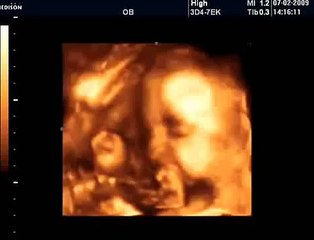

www.cemturan.combr www.dr-cemturan.combr www.jinekolojikonkoloji-istanbul.combr www.perinatoloji-istanbul.combr Hamilelikte renkli Doppler ultrason niçin yapılır? Bebek renkli mi görülür yoksa damarları görmek için mi renkli Doppler yapılır? Prof. Dr. Cem Turan'dan izleyin. Renklli doppler ultrason ile en çok incelenen damar bebeğin göbek kordonundaki damarlardır (umblikal damarlar). Bunun dışında rahim damarları, beyin damarları, kalp damarları gibi çeşitli damarlar incelenebilir. Özellikle rahim içerisinde gelişme geriliği (iugr) şüphesi olan bebeklerde, anomali varlığında, kalp ritm bozukluğu veya kardiyak anomali varlığında, yüksek tansiyon hastalarında yapılır. Her gebelikte rutin olarak yapılan bir inceleme değildir.